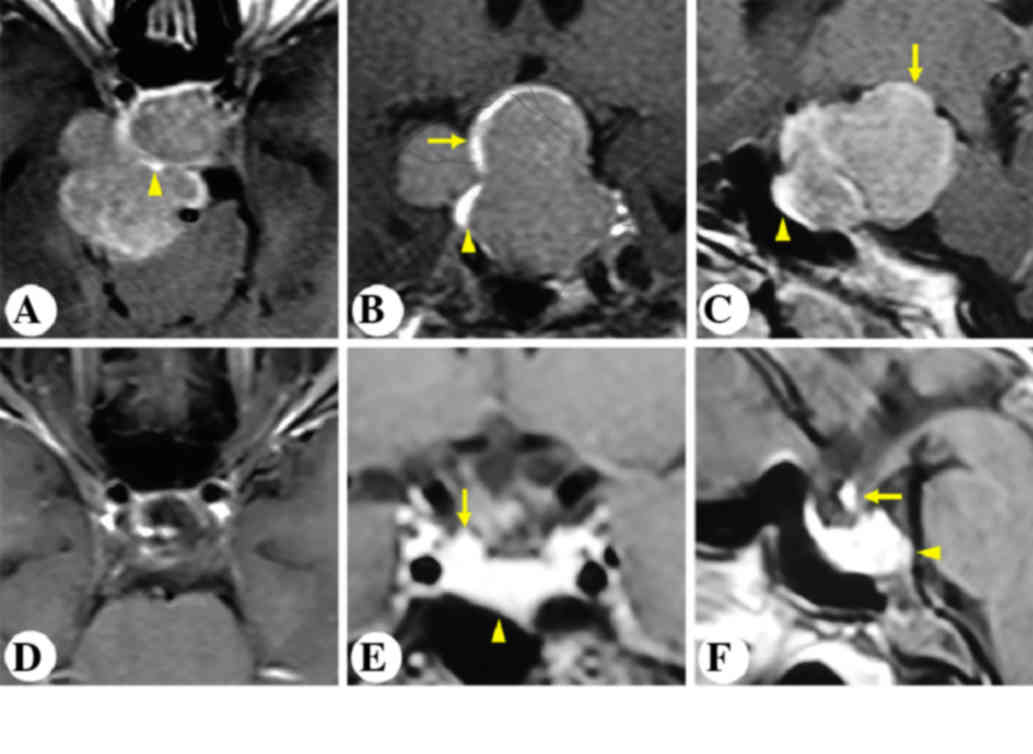

Case 5

A 33-year-old female was diagnosed with acromegaly three years ago. Pituitary hormone panel suggested a growth hormone secreting adenoma. Preoperative MRI showed a homogenously enhancing intra-, supra-, and parasellar lesion with a multilobular configuration (Fig. 6A-C). The stalk was compressed, distorted and displaced posterolaterally to the right. The gland was also displaced anterolaterally to the same side (Fig. 6A-C). The patient underwent pterional craniotomy. Following tumor excision, the pituitary stalk was visualized between the right optic nerve and the right internal carotid artery (Fig. 2D). Postoperative MRI showed gross total removal of the tumor and an anatomically intact gland and stalk (Fig. 6D-F).

Figure 6.

Patient 5. Representative post contrast T1-weighted images. Preoperative (A) horizontal, (B) coronal and (C) sagittal and postoperative (D) horizontal, (E) coronal and (F) sagittal magnetic resonance imaging of the sellar region. Arrows indicate the pituitary stalk. Arrowheads indicate the pituitary gland.